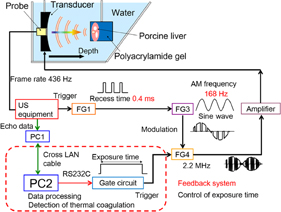

The transducer assembly was mounted on an arm and introduced into a water tank facing the target liver tissue, which was embedded in polyacrylamide gel. The acoustic properties such as sound speed and acoustic impedance of the polyacrylamide gel and water are almost identical. The porcine liver and polyacrylamide gel were degassed by a degasifier (SIBATA WJ-20). Polyacrylamide gel was constituted by mixing the materials shown in Table I. The HIFU transducer was excited at its central frequency by modulated bursts generated using three function generators (NF WF1974 and WF1946) and then amplified with a RF amplifier (E&I 2100). The schematic of the experimental setup for the LMI system is shown in Fig. 2. Figure 3 shows the timing diagram for the LMI experiment.

Fig. 2. Schematic of experimental setup.

Download figure:

A real-time, one-dimensional LMI monitoring system using a ring buffer memory was constructed. Signal and image processing were implemented with Matlab code on a windows-based PC. On the basis of real-time LMI, a prototype feedback control system was constructed. The schematic of this system is shown in Fig. 5.

Fig. 5. Schematic of experimental setup for real-time feedback control system using LMI.

Download figure:

Standard image High-resolution imageSixteen frames (corresponding to one period of LMI oscillation) of RF data obtained by an ultrasound scanner were acquired within 0.05 s in every 1 s. The computation time for data processing including cross-correlation was within 0.9 s. This sequence is shown in Fig. 6. HIFU ablation time was controlled using a gate circuit based on the results of LMI. The target was porcine liver tissue embedded in polyacrylamide gel. The experiments were conducted at room temperature. In this experiment, the AM frequency was 168 Hz. The HIFU frequency and intensity were 2.2 MHz and 1.2 kW/cm2, respectively. The beam propagation distances L shown in Fig. 7 are 10, 20, and 30 mm. The experiments were conducted as follows: